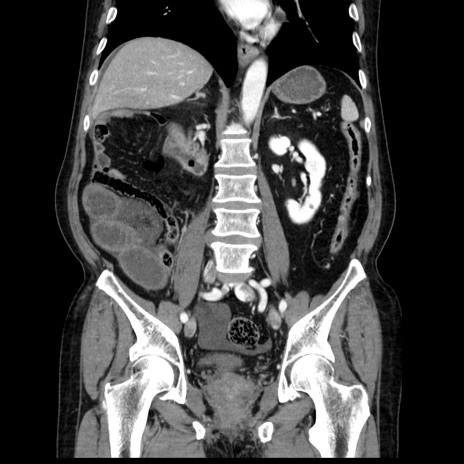

症例30(冠状断像)

【症例】80歳代男性

【主訴】臍周囲痛

【現病歴】約6時間前から臍下部痛が出現。次第に腹部膨隆・背部痛も生じてきたため来院。背部痛の場所は変化しない。

【身体所見】意識清明、BT 36.3℃、BP  131/87mmHg、P 87bpm、SpO2 100%(RA)、臍周囲自発痛・圧痛あり、反跳痛なし、自発痛部位に一致して板状硬あり、腹部膨隆、腸雑音減弱、CVA tenderness両側陰性。

【データ】WBC 19600、CRP 0.33